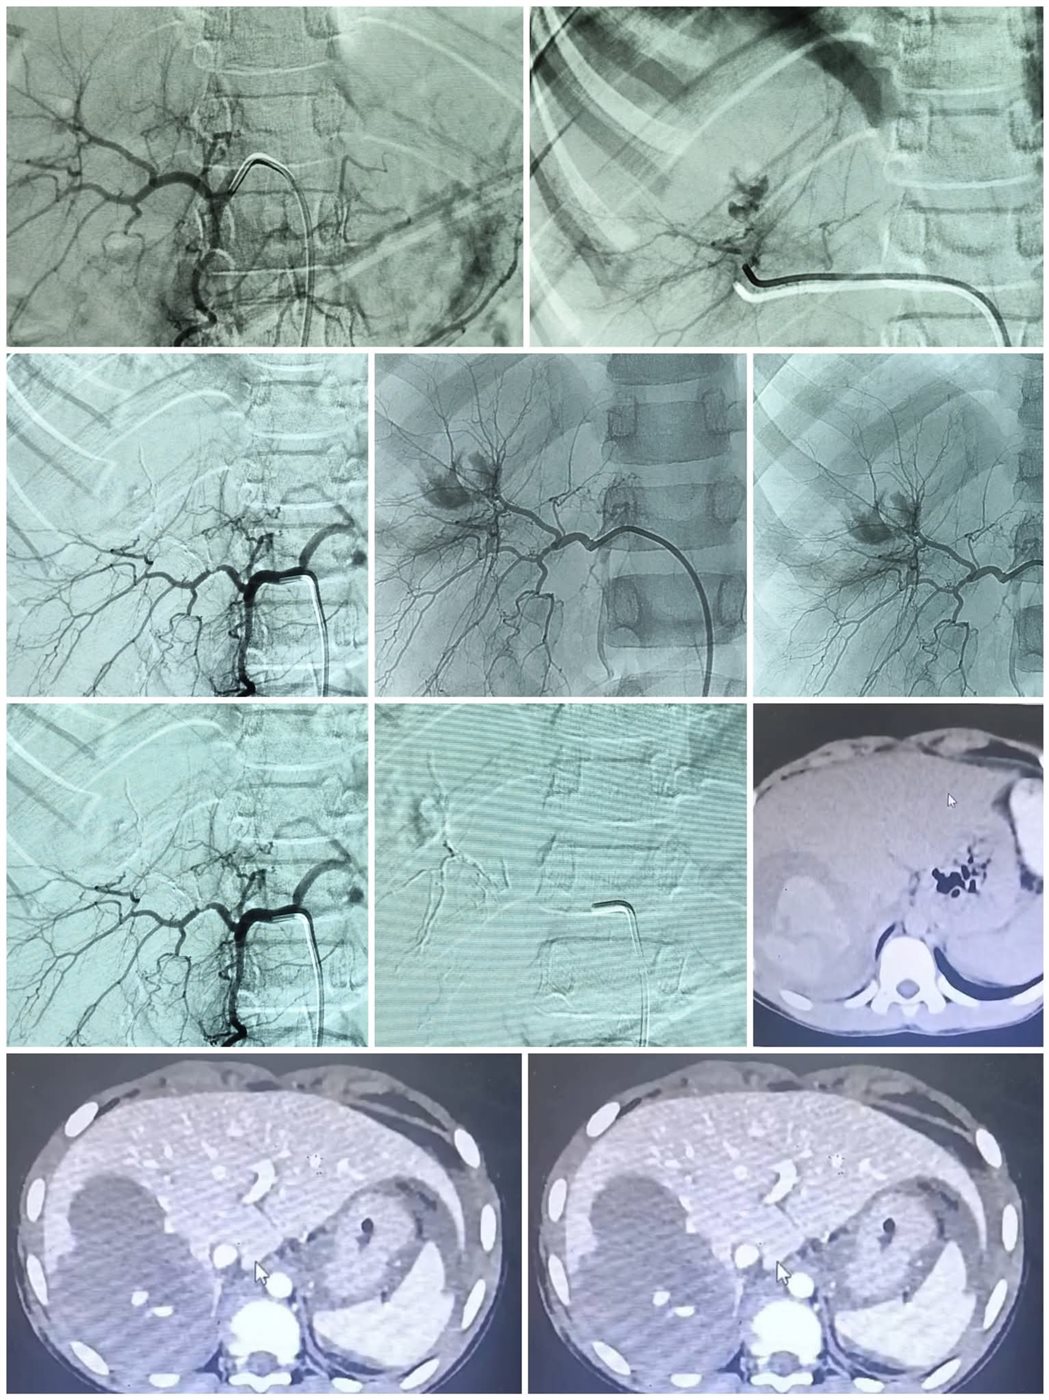

كان المستشفى، برئاسة الأستاذ الدكتور محمد عبد الحميد، قد استقبل طفل مصابا بإصابات متفرقة بعد حادث كان يقود فيه دراجة نارية "موتوسيكل"، ويعاني من تمزق حاد في الكبد أدى إلى قطع شرياني ونزيف داخلي عنيف ومهدد للحياة.

استدعى الوضع تدخلا سريعا ودقيقا، حيث يتم نقل المريض للمستشفى الرئيسي برئاسة الأستاذ الدكتور خالد عبد العزيز، ليقوم الفريق الطبي بقسم الأشعة، الذي جاء تحت إشراف الأستاذ الدكتور حسن إبراهيم مجلي، رئيس قسم الأشعة التشخيصية والتداخلية، والأستاذ الدكتور مصطفى هاشم، أستاذ الأشعة التشخيصية والتداخلية، وضم كل من الدكتور حمدي محمد إبراهيم، أستاذ مساعد الأشعة التشخيصية والتدخلية، والطبيب مصطفى طارق خلف الحسيني، أخصائي الأشعة، عاونهم الطبيب أحمد محمد حسين، طبيب مقيم بقسم الجراحة، والطبيب عمر المختار عبد العزيز، طبيب الطوارئ، ومن هيئة التمريض الأستاذ شعبان رمضان، والأستاذ عماد ناصح، فني بقسم الأشعة، استخدام تقنية القسطرة الشريانية التداخلية، وهي إجراء يتطلب مهارة عالية ودقة متناهية، وقد نجح الفريق في تحديد موقع النزيف الشرياني وإيقافه بشكل، مع الحفاظ التام على سلامة باقي الشرايين المغذية للكبد، ليعلن الفريق الطبي عقب ذلك استقرار حالة الطفل.

يعد هذا الإجراء من التدخلات الطبية المتقدمة التي تجنب المريض الجراحة المفتوحة المعقدة والمحفوفة بالمخاطر في حالات النزيف الحاد.